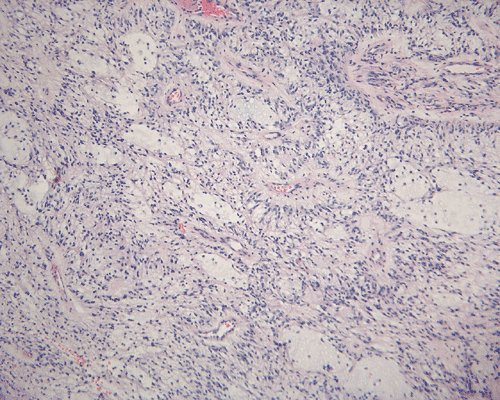

In a substantial amount of area, the tumor is composed of spindle cells with prominent perivascular arrangment and microcyst formation (Panel A and B). These vessels are surrounded by a thin rim of bipolar spindle cells (Panel C). The paucicellular perivascular mantle that is typical for ependymoma is absent in these perivascular arrangements. Adjacent to these perivascular arrangment is substantial amount of myxoid changes. On high-magnification, the tumor cells appear bland in histology, bioplar and spindle in shape, and admixed with a large amount of myxoid substance (Panel D and E). There is a lack of mitosis or significant pleomorphism. In some areas, the tumor is composed exclusively of spindle cells in a myxoid background with microcyst formation but without perivascular coronary arrangement of tumor cells (Panel F). It is not uncommon to observe areas with spindle cells clinging to the blood vessels (Panel G). In a minority of areas, there is increase in cellularity (Panel H). Some vessels seem to be composed of glomeruloids of blood vessels with plump endothelial cells (Panel I).

Histologically, the salient features of PMA are rather monotonous, small, spindle bipolar cells with angiocentric arrangement within a strikingly myxoid background. The myxoid basckground material is positive for Alcian blue but negative for PAS 1, 3,.  These features are well illustrated in our case. Occasional necrotic foci and mitotic figures can be present. Atypical mitotic figures and substantial nuclear pleomorphism should not be seen. Occasionally, the tumor cells infiltrate the surrounding non-neoplastic brain parenchyma but neither the histological feature nor radiological features would suggest a diffusely infiltrating astrocytoma. In contrast to pilocytic astrocytomas, PMAs do not possess a true alternating densely packed-loosely packed biphasic pattern, do not contain eosinophilic granular bodies or Rosenthal fibers 1, 4. Development of features that are seen in pilocytic astrocytomas such as the biphasic pattern and Rosenthal fibers have been described by Fernandez et al 4. These features are uncommon at the initial presentation but they can develop after chemotherapy. Although these features may suggest maturation of the tumor after chemotherapy, no association with improved prognosis has been described in the study by Fernandez et al 4. The angiocentric arrangement of tumor cells is another trap as it would suggest ependymoma. However, these arrangements are more irregular and fibrillar than the perivascular rosettes in ependymomas.